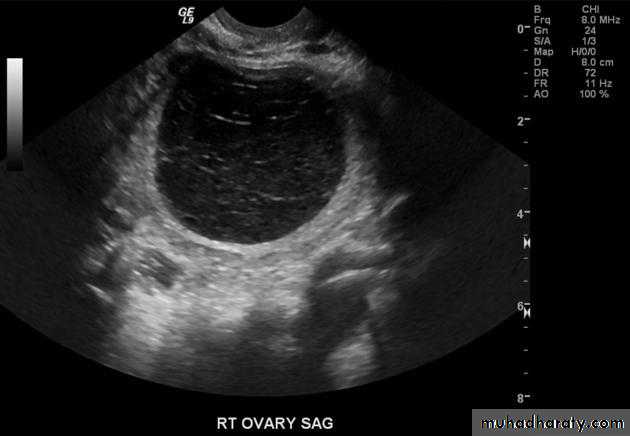

Ovarian cysts :

Ovarian cysts are commonly encountered in gynecological imaging, and vary widely in etiology, from physiologic, to complex benign, to neoplastic.

Small cystic ovarian structures should be considered normal ovarian follicles unless the patient is pre-pubertal, post-menopausal, pregnant, or the mean diameter is >3.0 cm

Radiographic features

Ultrasound is usually the first imaging modality for assessment of ovarian lesions. Simple ovarian follicular cysts are:

anechoic

intraovarian or exophytic;

have an imperceptible wall